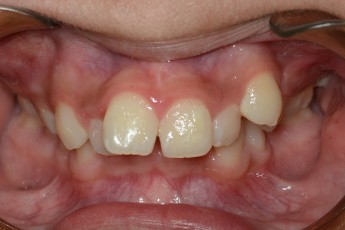

Before

After